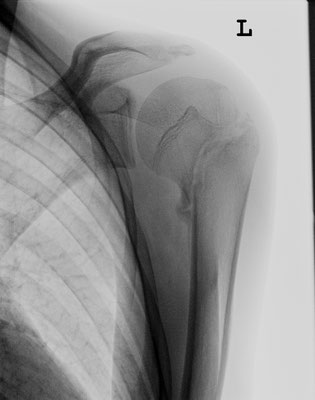

13-jähriger Junge mit Oberarmkopfbruch (Abb.1). Nicht operative Behandlung. Abb.2 zeigt das Röntgenbild nach 1 Jahr. Abb.3 zeigt die Funktion nur 2 Monaten nach dem Unfall!